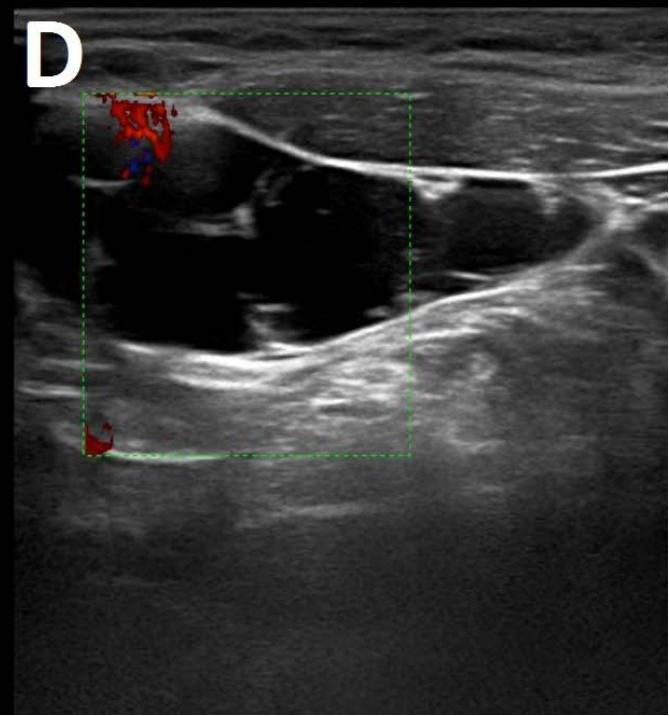

Figure/Patient 1

A 7 year-old girl presenting with a tumefaction at the level of the right latero-cervical region. US scans show a $43 \times 14$ mm subcutaneous fluid formation with septa extending from the root of the neck to the submandibular region (A-B). Doppler-mode demonstrates lack of blood flow within the lesion or the septa (C-D). Diagnosis of cystic lymphangioma is done.